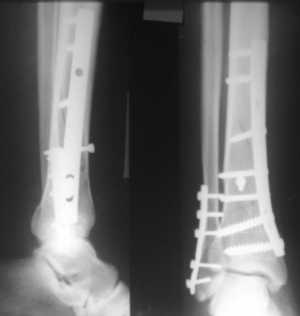

Хирургическое лечение

Оперативное вмешательство при лечении травмы лодыжки со смещением необходимо в следующих случаях:

- Переломы обеих щиколоток;

- открытые переломы лодыжки;

- разрыв межберцового соединения и сложные повреждения связок голеностопного сустава;

- невозможность проведения закрытой ручной репозиции при серьезных травмах;

- застарелые переломы;

- смещение фрагментов заднего нижнего отдела большеберцовой или малоберцовой кости более чем на 1/3 поверхности, сопровождающееся нарушением целостности щиколоток.

Существует несколько типов хирургических вмешательств при травмах лодыжки как со смещением, так и без него:

- Остеосинтез медиальной лодыжки. Эта операция выполняется при супинационных переломах. Медиальная лодыжка фиксируется с помощью двухлопастного гвоздя, установленного под прямым углом, а латеральная лодыжка дополнительно укрепляется штифтом. В некоторых случаях обломки фиксируются винтами.

- Скрепление межберцового соединения. Такие операции проводятся при переломах медиальной щиколотки и малоберцовой кости, а также при других травмах, сопровождающихся разрывом межберцового соединения.

- Остеосинтез фрагментов большеберцовой кости. Эти операции выполняются при травмах большеберцовой кости в задней области нижнего конца.

- Остеосинтез латеральной лодыжки. Показаниями для этой операции являются пронационные переломы.

После завершения хирургического вмешательства конечность фиксируется гипсом, который накладывается так, чтобы обеспечить доступ к послеоперационной ране для дальнейшей обработки. После операции обязательно выполняется контрольная рентгенография. Повторные снимки также проводятся в процессе реабилитации.